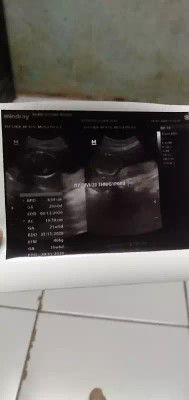

sedang mengandung